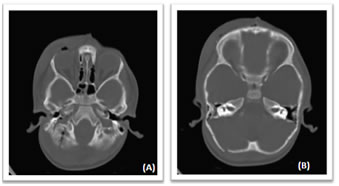

Figure5: Axial NECT scan: A 3-year old girl with history of falling down from Stairs, NCCT showing (A) right occipital bone fracture (B) hemotympanum and hemomastoid. Temporal bone fractured couldnot be shown.